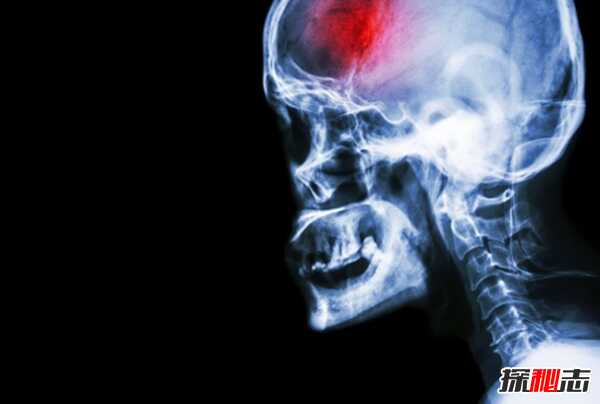

2、中风:每年624万人死亡

中风是当血液供应被血凝块切断时发生的,在处理中风患者时,时间是至关重要的,因为脑细胞在几分钟内就会死亡。